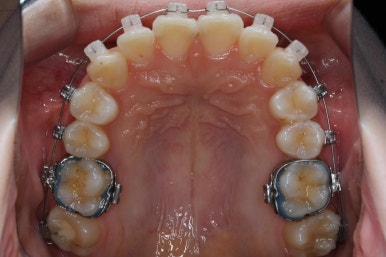

위 사진은 연산동교정치과 처음 내원하셨을 때의 입안 모습입니다. 몇 가지 모습이 관찰됩니다.

치아가 삐뚤삐뚤합니다.

위~아래 앞니가 많이 겹쳐서 아랫니가 많이 모이지 않는 "과개교합" 입니다.

앞니가 앞으로 뻐뜨러져 있습니다.